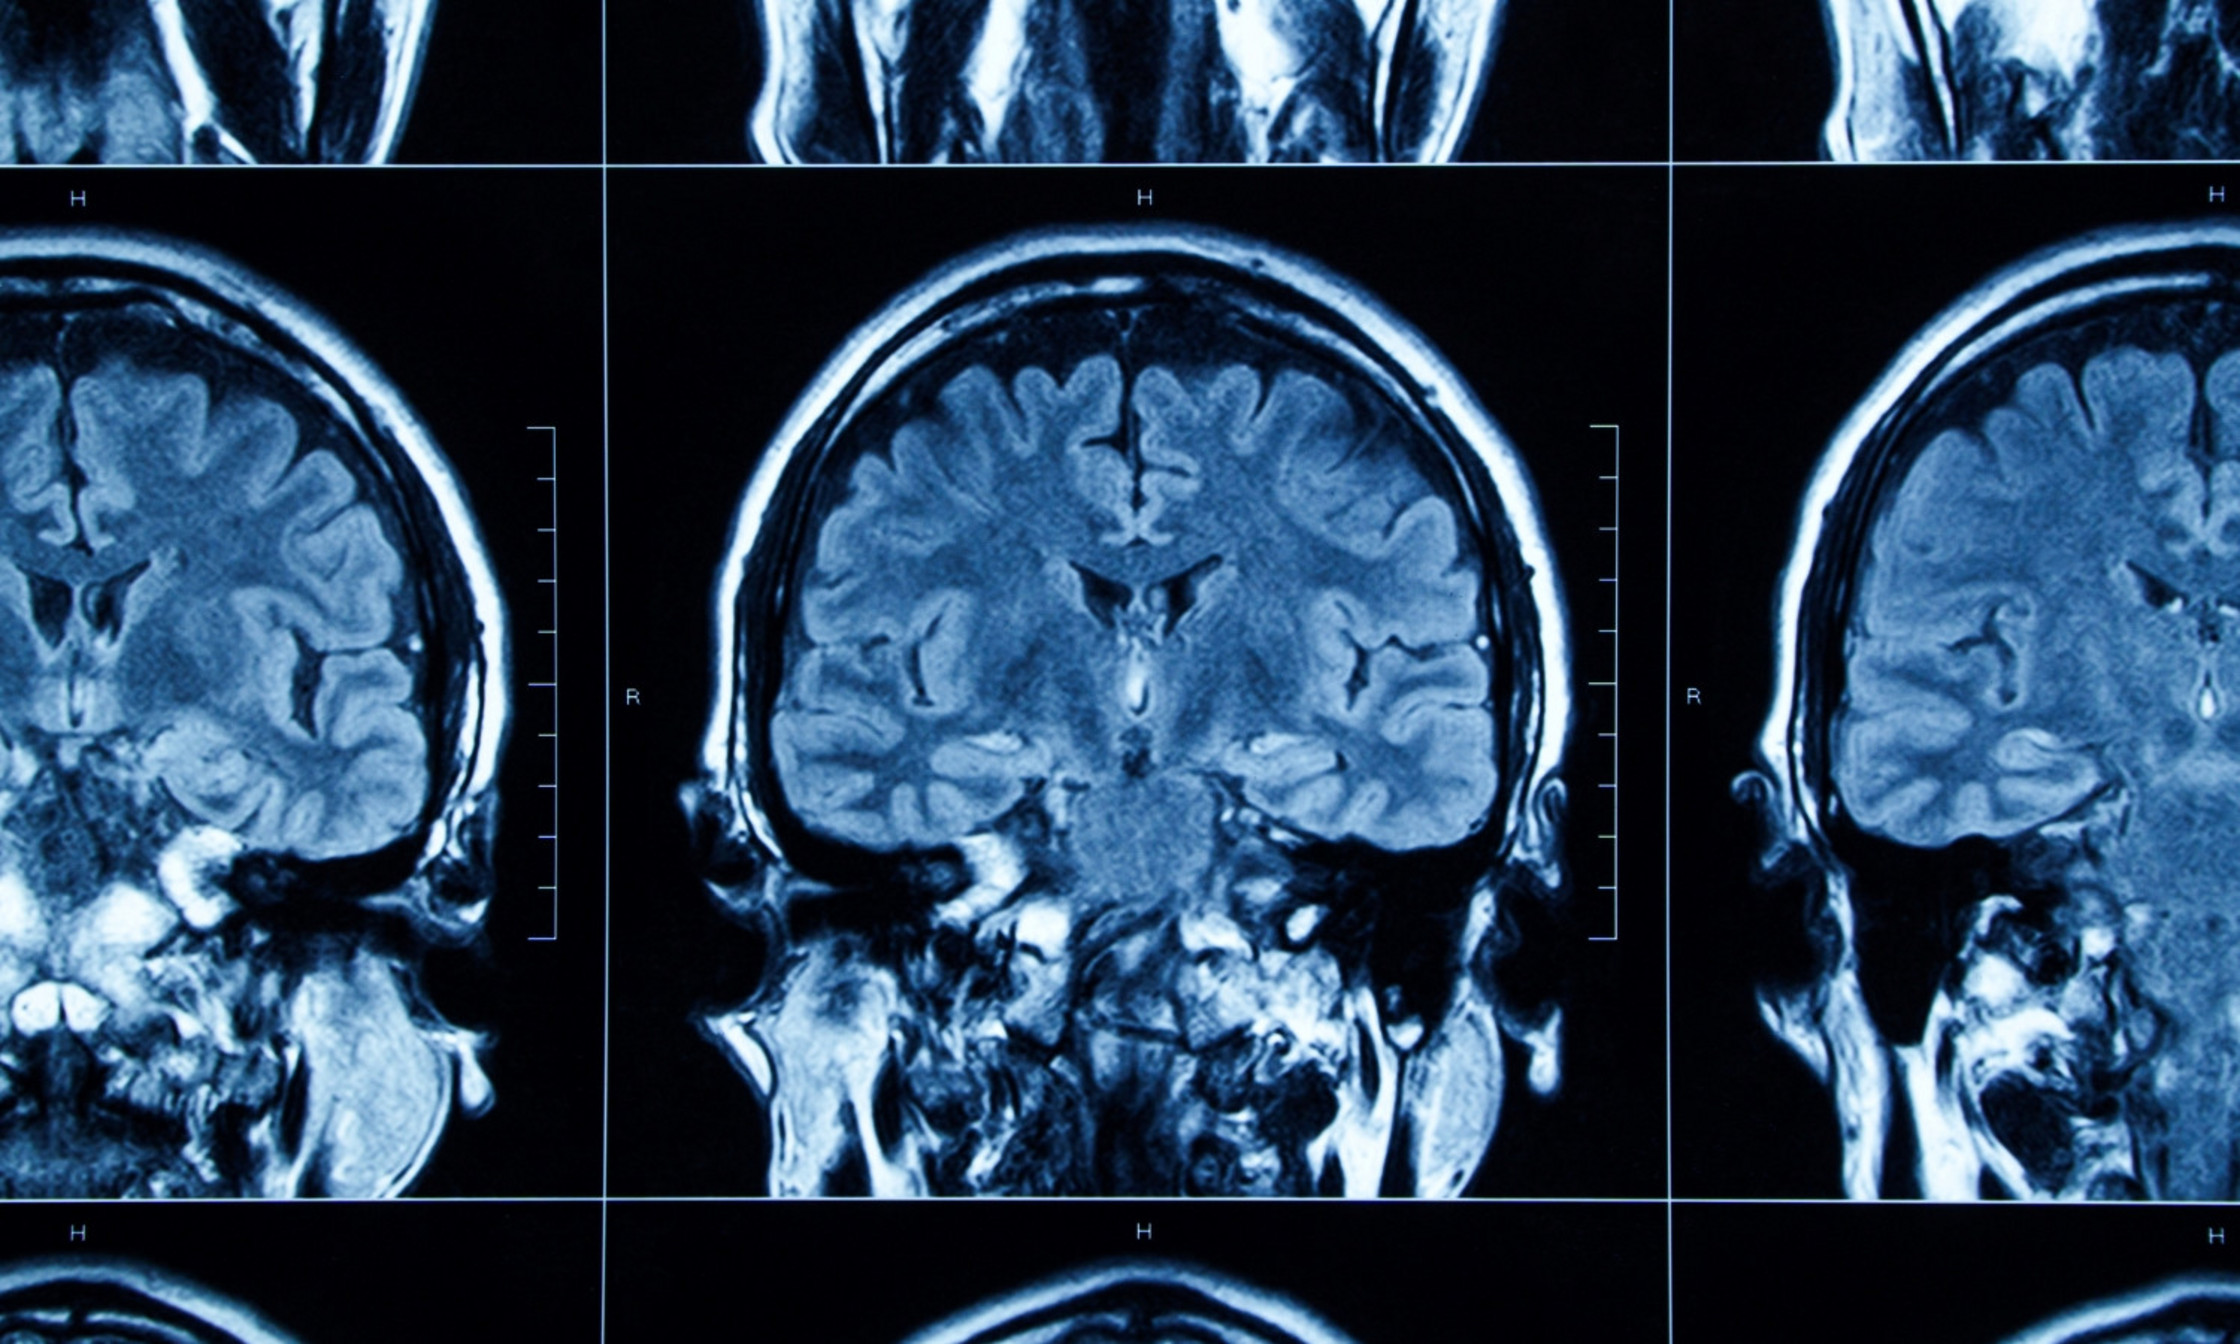

CARSM researchers have access to the largest database of patients with RBD. But to find a biomarker with the help of AI, Rahayel’s computational neuroscience team needed even more MRI brain scans.

Tracking down the information, they contacted 11 sleep study centres around the world to assemble a database of 1,276 MRI scans of people at risk of, or with, Parkinson’s disease or LBD, and also of healthy people.

Using machine learning and computational models, the researchers identified two trajectories of brain atrophy progression.

LBD seems to be associated with brain atrophy that begins in the cortex and then spreads to the interior of the brain, while in Parkinson’s the atrophy progresses from the interior to the exterior of the brain.